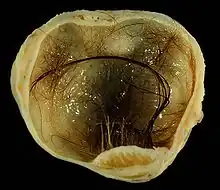

- Des tératomes ovariens peuvent produire des poils ou des dents à l’intérieur des ovaires, et éventuellement être associés à un goître[17].

- Certains tératomes produisent un mélange de tissus mûrs et bien différenciés : épithélium respiratoire, follicule pileux ; tissu adipeux ou tissu nerveux mûr.